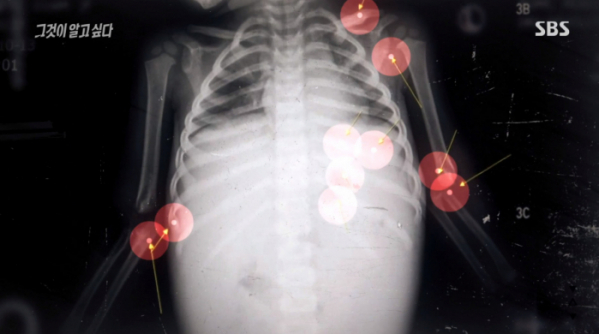

그는 "이 사진 등을 봤을 때 피가 거꾸로 솟는 듯한 느낌을 받았다. 그리고 이게 다 골절이다. 나아가는 상처, 막 생긴 상처. 이 정도 사진이면 교과서에 실릴 정도의 아동 학대 소견이다"라고 말했다.

이어 "아기들은 갈비뼈가 잘 안부러진다. 애들 만져보면 탱탱하고 신축성이 있다. 16개월이 갈비뼈가 부러진다? 이건 무조건 학대다"라고 덧붙였다.